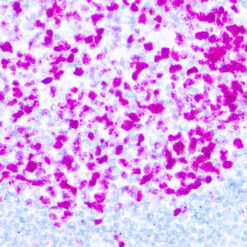

This antibody reacts with a 33-36 kDa protein known as ERCC1 (excision repair cross complementing) polypeptide. ERCC1 is required for nucleotide excision repair of damaged DNA and is homologous to RAD10. In mammalian cells, XPG cleaves 3’ of the DNA lesion while ERCC1-XPF complex makes the 5’ incision.

| Cellular Localization | Nuclear |

| Positive Control Tissue | Tonsil |